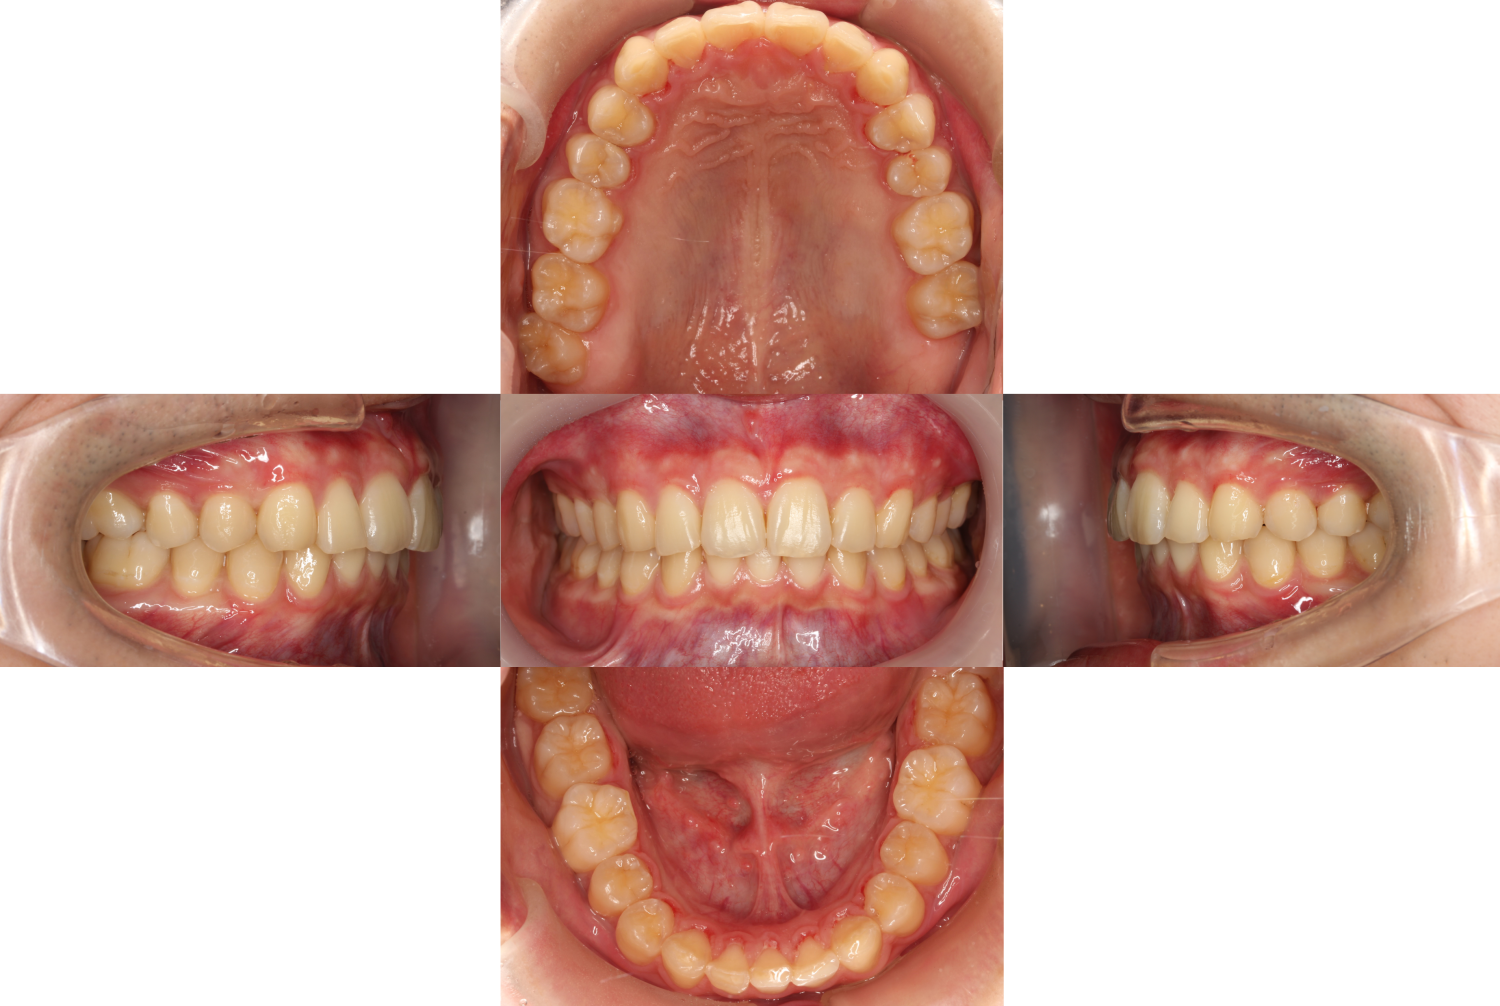

約1年11か月後

過蓋咬合・裏側矯正の症例

お悩みだった【凸凹、上の歯が出ている、上下の歯が噛み合わない】

等が改善しました。

また、右下2番欠損に合わせて左右、上下、噛み合わせのバランスも均等に仕上がりました。